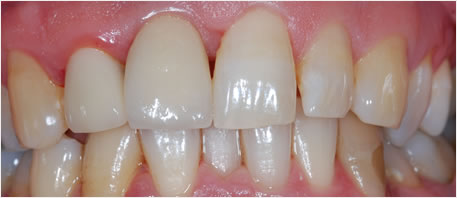

Before Dental Implant

dental implants northern ireland

After Dental Implant